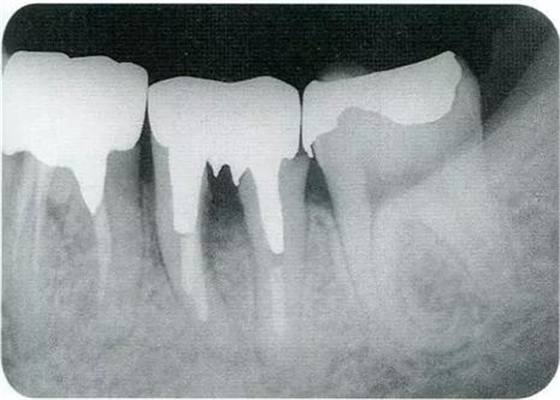

▼圖16-1 ▼圖16-2

圖16-1對(duì)右上6.7分叉部病變處理時(shí),對(duì)包括右上4.5進(jìn)行齦瓣分割,確認(rèn)骨缺失狀態(tài)。右上7頰側(cè)存在著12mm的骨緣下缺失。

圖16-2右上6水平的分叉部病變到達(dá)了III度。